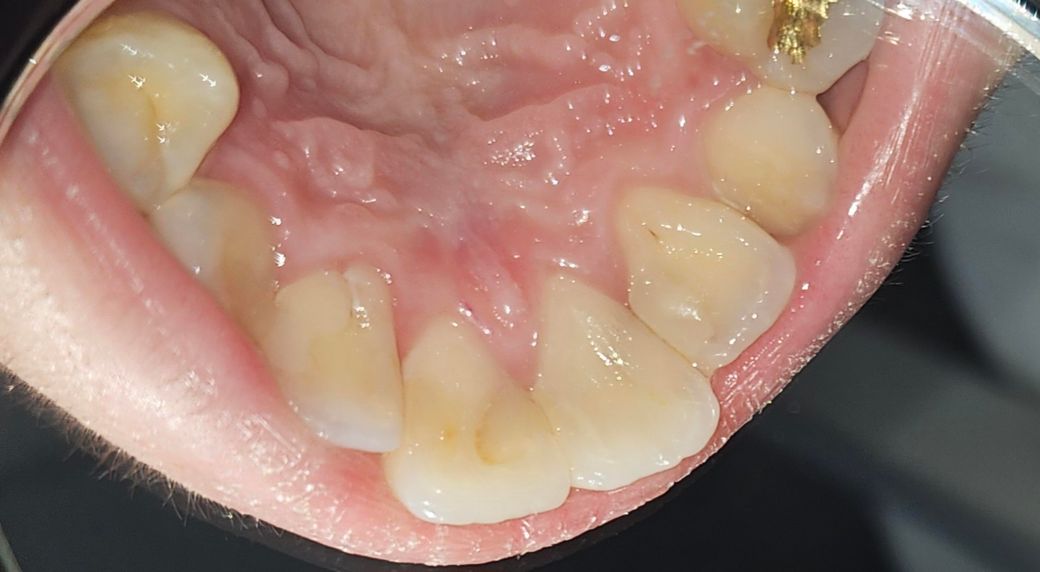

대문니 옆 작은대문니 뒤쪽 까만점 충치인가요?

앞니들 치료는 2월경에 했고 엑스레이는 11월에 찍었었는데 별다른 이상은 없었어요.

통증도 따로 없구요. 그런데 오늘 보니 양옆 작은대문니 뒤쪽? 뿌리쪽에 까만점이 보이는데 이거 충치인가요? 낮에만해도 안보였던 것 같은데 갑자기 보이네요

대문니와 양쪽대문니등에 충치가 있는건지 궁금합니다.

• 1번 째 사진